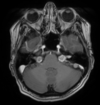

Qual o padrão da imagem na AMS-C?

A

Atrofia de cerebelo (vermis) e tronco (principalmente ponte); Hipersinal T2 na ponte: Sinal da cruz na ponte (não patognomônico), perda da barriguinha da ponte, Hipersinal nos pedúnculos cerebelares médios;